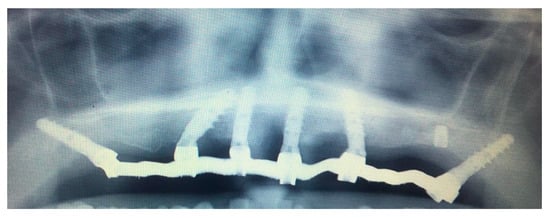

3.1. SCAI Approach Clinical Case